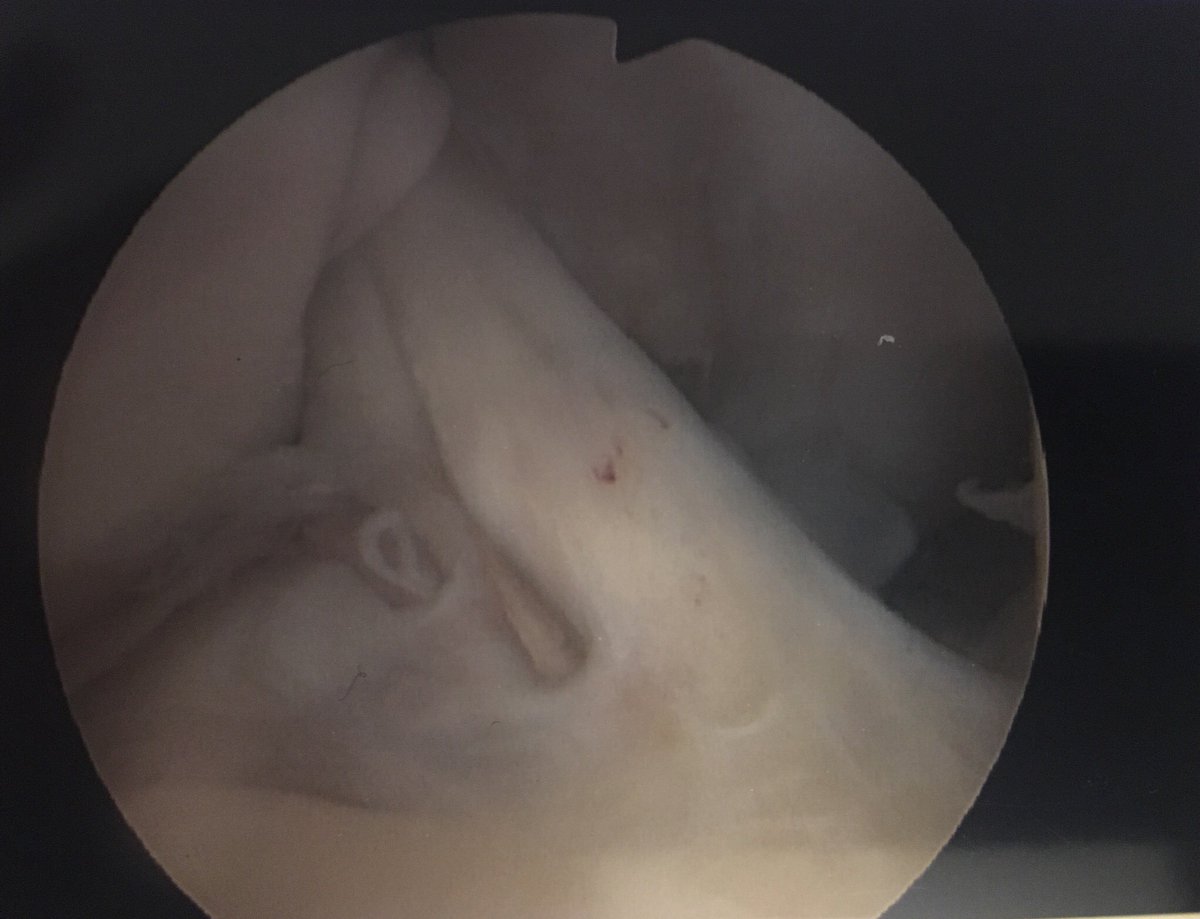

1 year post ACL reconstruction, 2 surgeries and I have been cleared by my surgeon!! Below is my new healthy ACL. What a journey. It’s far from over though. Time to smash those quad/hamstring ratios with Stronglines Physio💪🏻. The comeback is on⚽️. Thank you for all the amazing support❤️

1 year post ACL reconstruction, 2 surgeries and I have been cleared by my surgeon!! Below is my new healthy ACL. What a journey. It’s far from over though. Time to smash those quad/hamstring ratios with <a href="/SL_Physio/">Stronglines Physio</a>💪🏻. The comeback is on⚽️. Thank you for all the amazing support❤️